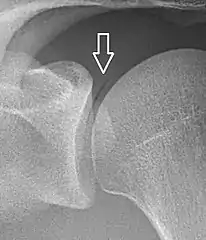

Pneumarthrosis is the presence of air in a joint. Its presentation on radiography is a radiolucent cleft often called a vacuum phenomenon, or vacuum sign.[30] Pneumarthrosis is associated with osteoarthritis and spondylosis.[31]

Pneumarthrosis is a common normal finding in shoulders[30] as well as in sternoclavicular joints.[32] It is believed to be a cause of the sounds of joint cracking.[31] It is also a common normal post-operative finding at least after spinal surgery.[33] Pneumarthrosis is extremely rare in conjunction with fluid or pus in a joint, and its presence can therefore practically exclude infection.[31]